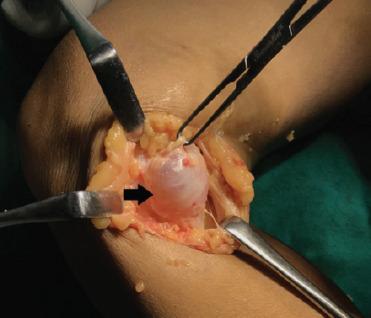

We report a case of a large symptomatic medial parameniscal cyst in 52-year-old female which was clinically misdiagnosed as Baker's cyst. The patient had swelling over the posteromedial aspect of the right knee with difficulty and pain on squatting. Magnetic resonance imaging (MRI) reported horizontal tear in the posterior horn of medial meniscus and parameniscal cyst adjacent to medial meniscus with features of early osteoarthritis of the knee. She was successfully treated with open excision and repair of the defect of the cyst along with arthroscopic partial medial meniscectomy.

This case highlights the importance of MRI in diagnosis and planning and the use of a combined approach for successful management of large parameniscal cyst.